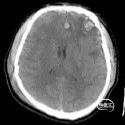

辅助检查:入院当天头部CT示:双侧额顶叶、左侧颞叶脑挫裂伤,最大截面约3.05×2.30cm,蛛网膜下腔出血。